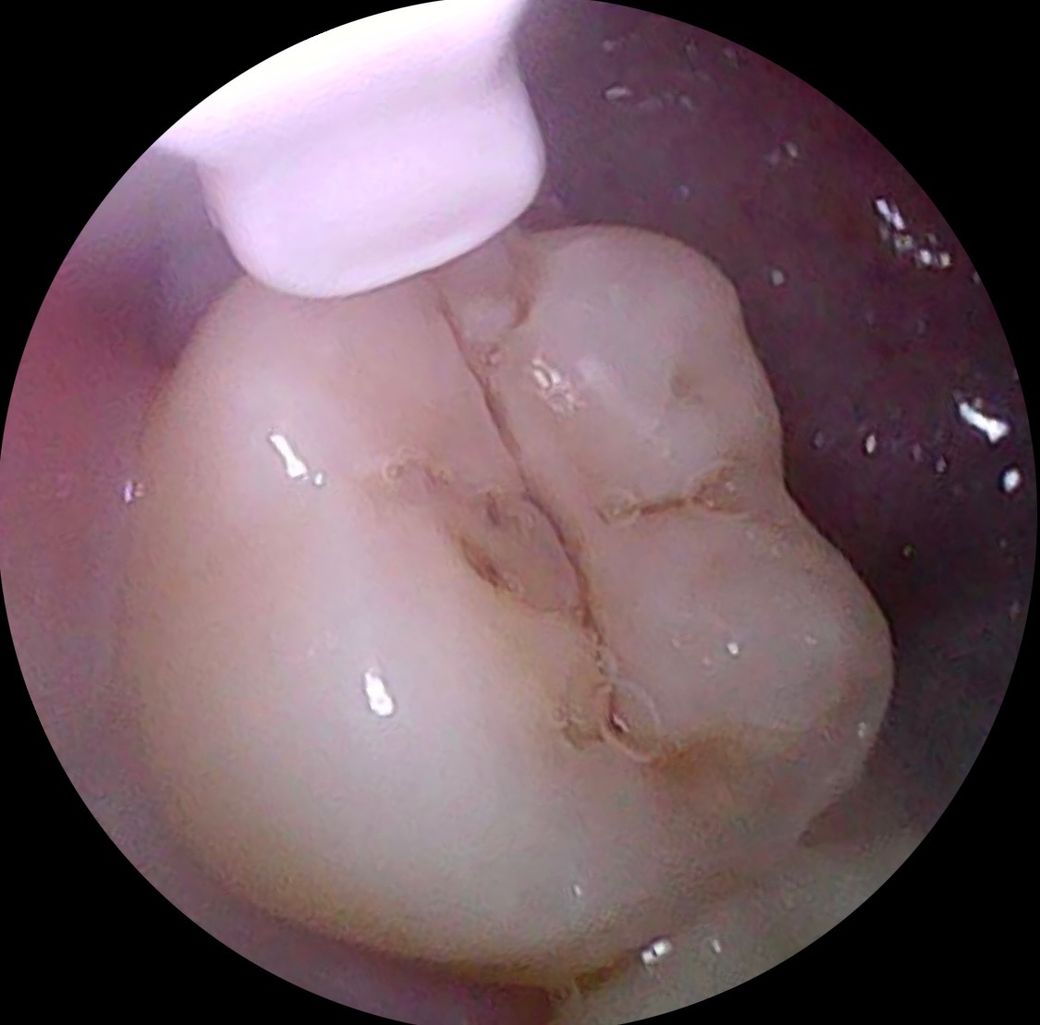

1번 사진은 제가 봐도 많이 썩은 거 같아요. 사랑니인데, 곧 뽑으러 갈 예정입니다!

• 1번 째 사진